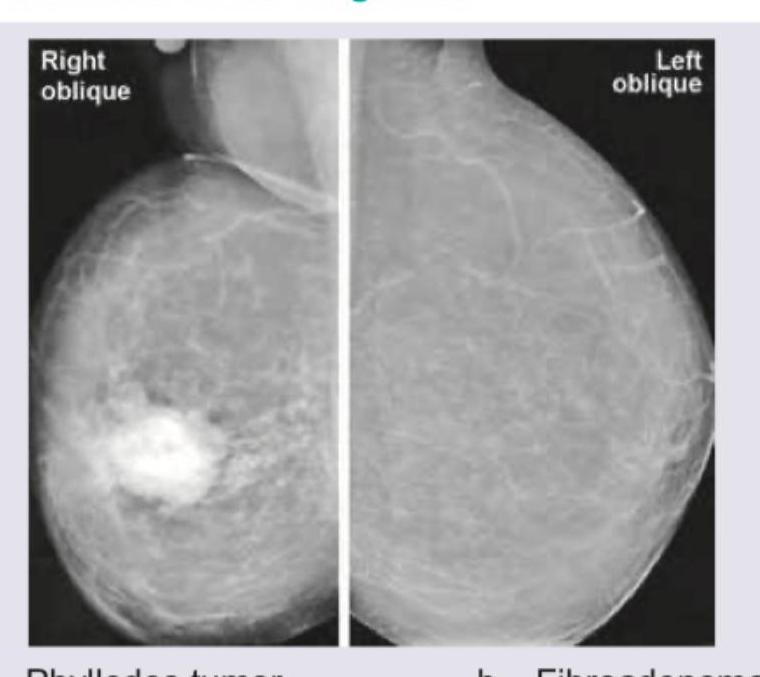

A 35-year-old woman presents with a rapidly enlarging palpable breast mass over the past 3 months. Mammography is performed. What is the most likely diagnosis?

Explanation: ***Phyllodes tumor*** - The mammogram shows a **large, well-circumscribed, lobulated mass** with areas of increased density and possibly some calcifications, which is characteristic of a phyllodes tumor. - Phyllodes tumors are **biphasic fibroepithelial tumors** that can grow rapidly and tend to be larger than fibroadenomas, often presenting as palpable masses with a rapidly increasing size. *Fibroadenoma* - While fibroadenomas are also well-circumscribed, they are typically **smaller** and less lobulated than the mass seen in the image. - They often contain distinctive **"popcorn" calcifications** which are not clearly depicted here, and rapid growth is a less common feature. *Galactocele* - A galactocele is a **milk-filled cyst** that usually occurs in lactating or recently pregnant women. - Radiographically, it appears as a **well-defined, low-density mass** that can be challenging to differentiate from a fat lobule or lipoma, but it would not typically have the dense, solid-appearing components seen here. *Carcinoma breast* - Malignant breast tumors, especially invasive carcinomas, typically present with **spiculated margins**, irregular shapes, and architectural distortion, or suspicious microcalcifications. - The mass in the image, although large, is relatively **well-circumscribed** and does not exhibit the classic malignant features like spiculations or architectural distortion.